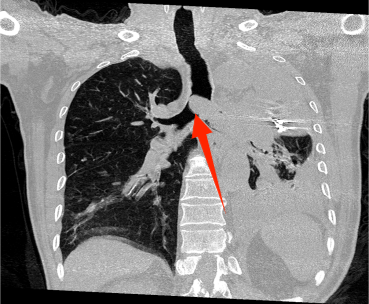

近年来,贵州航天医院各科室紧跟医学前沿,不断强技术、补短板,大力开展新技术、新项目,完成了许多高精尖、高难度、本地区“首例”的技术,填补了医院医疗技术空白,满足了群众日益增长的医疗需求。 贵州航天医院呼吸与危重症医学科是贵州省内呼吸疾病治疗规模最大,诊疗项目最全的呼吸疾病品牌科室,呼吸介入技术达到了全国先进水平,在贵州省内处于领先的地位。 本期,我们将为大家带来呼吸与危重症医学科特色技术——气道支架置入技术治疗呼吸不畅(已纳入乙类医保报销)。 案例分享 一患者因出现呼吸困难、气急等症状,听说我院呼吸与危重症医学科呼吸系统疾病诊疗实力在省内属于前列,慕名前来就诊,入院后,呼吸与危重症医学科为患者完善了胸部CT检查,提示:左主支气管肿瘤生长至气管下段,左肺不张,对此,科室立即组织多学科(MDT)讨论,对患者进行全面的诊断评估,诊断为:左肺鳞癌,左肺不张,气管下段内生型狭窄,左主支气管堵塞。 在充分了解患者及家属的治疗需求和征得治疗同意后,为进一步减轻患者呼吸困难症状,决定为患者实施气道支架置入技术,通过将支气管镜插入到气管中,使用气道球囊扩张器对狭窄的气道进行扩张,在病变部位置入支架扩张狭窄的支气管后,患者安全返回病房。 国产镍钛记忆合金支架植入步骤 术后,患者左主支气管通畅。 什么是气道支架置入技术 气道支架置入技术是一种用于治疗气道狭窄及气道相关性瘘等疾病重要的手段,尤其适用于因恶性肿瘤或其他原因导致的呼吸困难患者。是利用一种保持管腔完整性的人造装置——支架并应用支架置入器在X线透视或支气管镜直视下将支架置入气道保持气道通气功能的一种方法。 目前气道支架最常见的类型有可膨胀金属气道支架、硅酮支架及混合性支架等,以可膨胀金属支架为最常用。 气道支架置入技术原理 是将具有一定张力和弹力的支撑物(即气管支架)置入气道内,将狭窄或塌陷的气道撑开,从而维持气道通畅,或堵住破裂的瘘口。根据气管、支气管不同部位的解剖特点和病变情况,选择对应型号的支架,并通过气管镜的指引,在病灶位置植入合适的支架,也可根据气道的收缩性、不规则性和狭窄程度,进行适当调整。 气道支架置入技术优势 (一)快速缓解呼吸困难:支架置入能够迅速撑开狭窄或塌陷的气道,显著改善患者的呼吸困难症状。 (二)降低气道塌陷风险:对于某些肿瘤或炎症引起的气道狭窄,支架置入可以稳定气道结构,降低气道塌陷和窒息的风险。 (三)创伤小、恢复快:相较于传统手术,气道支架置入术具有微创的特点,患者术后恢复较快,痛苦较小。 气道支架可减轻或抵抗外部压力,扩大狭窄气道后,中央气道梗阻的症状和体征可立即减轻或消除,肺功能、运动能力及生活质量也得到改善。理想的气道支架应具备对气道壁物理性刺激小、置入后不移位、能阻止肿瘤或组织向支架内生长、不影响排痰、可以并容易回收等特点。 贵州航天医院 呼吸与危重症医学科专家团队 廖江荣 国务院政府特殊津贴专家 二级教授 主任医师 贵州航天医院副院长 国家级学术任职: 第二届中国医药教育协会介入微创专业委员会呼吸分会副主任委员 中国抗癌协会肿瘤微创治疗专业委员会常务委员 中国防痨协会结核病转化医学专业分会常务委员 第一届中国人体健康科技促进会呼吸介入专委会常务委员 中国医疗保健国际交流促进会结核病学分会第三届委员会常务委员 中国抗癌协会肿瘤微创治疗专业委员会粒子治疗学组第四届委员会委员 中华医学会结核临床专业委员会内镜介入委员 中华医学会放射学分会第十五届委员会介入学组呼吸系统介入专业委员会委员 北京健康促进会中青年专家委员会胸部疾病精准活检分委会副主任委员 中国医师协会介入医师分会第二届委员会肿瘤消融专业委员会委员 中国结核病防治综合质量控制专家指导委员会委员 亚洲冷冻治疗学会常务委员 世界内镜医师协会呼吸内镜协会常务理事 内镜临床诊疗质量评价专家委员会委员 “西部呼吸介入联盟”副理事长 专业擅长: 呼吸系统(肺)疑难病的诊断及危重病的抢救,呼吸系统(肺)感染性、疑难性疾病介入快速诊断(ROSE),尤其在肺癌、肺小结节早期诊断,肺癌微创综合靶向治疗,难治性、复治性、重症肺结核诊疗,硬质支气管下复杂性气道狭窄诊治,纤支镜介入治疗气道肿瘤、结核、气道狭窄(球囊扩张、支架植入、高频电刀、氩气刀、冷冻、灌洗、注药、微波消融),间质性肺疾病的诊疗上具有极高水平;带领团队勇于创新,在贵州省率先开展多项新技术、新疗法,如CT引导下及纤支镜下I125粒子植入及CT引导下微波、射频消融介入治疗肺癌等多项新技术,带动了贵州省肺部疾病的介入治疗水平提高。 蒋 婷 呼吸与危重症医学科 总负责人 副主任医师 专业擅长:从医20余年,在呼吸系统疾病、介入呼吸病学、肺部结核、肺部肿瘤等方面具有丰富的临床经验和专业技能,尤其是慢性阻塞性肺疾病、支气管扩张、肺结核、耐药肺结核、肺癌、胸腔积液等肺部疾病的诊治、微创介入、危重病患者抢救。 现任中国防痨协会人兽共患结核病专业分会委员,中国女医师协会第一届介入专业委员会委员,贵州省基层呼吸疾病防治联盟-间质性肺疾病联盟委员,贵州省防痨协会第七届理事会理事,贵州省中西医结合学会呼吸专业委员介入呼吸病学组委员,贵州省遵义市中医药学会中西医结合肺病(呼吸)分会副主任委员,贵州省遵义市中医药学会中医肿瘤专业委员会常委;发表论文数篇,参与并主持多项科研项目。 李桂凤 呼吸与危重症医学科 三病区 主任 副主任医师 专业擅长:从事呼吸系统疾病、结核病学、介入呼吸病学、肿瘤综合治疗、呼吸康复等临床工作20余年,擅长呼吸内科常见病、多发病及疑难重症危重病症的诊治,尤其对重症疑难结核及耐药结核病、介入治疗(肺)呼吸系统疾病、呼吸危重病抢救等方面具有较高诊疗水平。 中国防痨协会非结核病专业委员会委员,贵州省中西医结合学会第六届呼吸专业委员会委员,贵州省康复学会睡眠障碍康复专业委员会委员,遵义市呼吸内科医疗质量控制中心委员,遵义市落实民生实事结核病筛查阅片专家组成员;主持及参与实用新型专利3项。 周裕祥 呼吸与危重症医学科 四病区 主任 副主任医师 专业擅长:经皮肺介入、经血管介入诊疗技术。 贵州省中西医结合学会呼吸专业委员会介入呼吸病学组常务委员,中国医师协会呼吸医师分会介入呼吸病学工作委员会呼吸病血管介入学组委员,贵州省中西医结合学会呼吸学分会委员,遵义市医学会放射肿瘤治疗学分会委员,中国医药教育协会介入微创呼吸分会委员,北京健康促进会中青年专家委员会胸部疾病精准活检分委会委员;曾赴重庆医科大学RICU、珠海市人民医院介入科进修学习。 杨 芳 呼吸与危重症医学科 内镜中心 主任 副主任医师 专业擅长:从事临床工作约16年,对呼吸危重病的救治有独到的见解,尤其擅长呼吸系统疾病的介入诊疗,对呼吸内镜下的诊治及经皮肺穿刺诊疗技术具有丰富的临床经验。 亚洲冷冻治疗学会委员,中国医药教育协会介入微创呼吸分会委员,西南结核病医院联盟第二届委员会秘书/委员,贵州省中西医结合学会第六届呼吸科专业委员会委员,贵州省中西医结合学会呼吸专业委员会介入呼吸病学组秘书,贵州省中西医结合学会呼吸专业委员会基层康复学组副组长,贵州水利电力医学科学技术会高原医学分会委员,遵义市中医院学会中西医结合肺病(呼吸)分会秘书/常务委员,遵义市医学会肿瘤学分会(第二届)委员,遵义市医学会放射肿瘤治疗学分会第二届委员;主持及参与科研课题多项,参编著作《呼吸内镜操作技术规范》、《介入结核病学》,发表论文数篇。 贵州航天医院 呼吸与危重症医学科专家团队 贵州航天医院呼吸与危重症医学科以呼吸危重症和介入呼吸病学为强力推手,以肺部感染性疾病及肺癌、肺小结节的早期精准诊疗、慢性呼吸疾病康复治疗为特色,以人才团队建设为核心的科室发展模式,现已成为省内呼吸疾病治疗规模最大,诊疗项目最全的呼吸疾病品牌科室。是贵州省医学重点学科、临床医学重点专科建设单位,遵义市首批呼吸重点学科、重点专科建设单位。是国家卫健委能力建设和继续教育肿瘤微创介入建设中心、贵州省县级医院微创介入培训中心、遵义市呼吸疾病临床医学中心。是国家呼吸医疗质量控制与管理哨点医院、遵义市呼吸内科专业医疗质量控制中心。是中国医药教育协会介入微创呼吸分会呼吸介入技术培训中心单位;国家卫健委海医会呼吸分会ROSE专委会“诊断性介入肺脏病学快速现场评价”培训基地;中国肺癌防治联盟“贵州航天医院肺结节诊治”分中心,中国人体健康科技促进会呼吸介入技术培训基地,贵州省中西医结合会呼吸学分会呼吸介入专委会主委单位。 基本情况 平均每年开展气管镜诊疗约4000例,经皮肺穿刺介入诊疗近千例,开展的项目包括经支气管镜(软、硬)下冷冻、氩气刀、高频电刀、球囊扩张、支架置入、超声内镜诊疗等气道介入诊疗技术,经皮肺穿刺活检及肿瘤消融术(微波、冷冻)、ROSE技术、内科胸腔镜诊疗及经血管介入诊疗技术,且多项呼吸介入诊疗技术在省内处于领先水平。 诊疗范围 致力于呼吸系统感染性、疑难性疾病的介入快速精准诊疗;肺癌与肺小结节早期精准诊疗水平项目提升。擅长于呼吸系统(肺)疑难病的诊断及危重病的救治,尤其在肺癌、肺小结节的早期诊断;肺癌综合靶向治疗;肺结核综合诊疗;肺部疾病的介入诊疗在省内处于前沿水平。